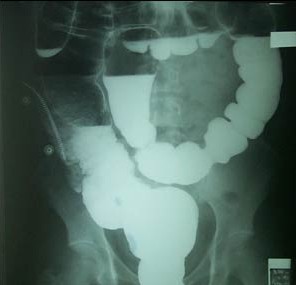

钡灌肠

当怀疑病人有结直肠的某些疾病(比如梗阻、溃疡、肿瘤等)时,便可采用此法。采用钡剂灌肠,从肛门注入稀释钡剂然后再打入少量气体,使得直肠、全部结肠及盲肠显影。 然后通过射线排除制剂在体内形成的形态变化来确定是否有占位及溃疡性疾病的一种方法、钡剂高密度,在射线通过时显白影,周围组织黑色,对比明显,容易分别。

包括单纯性钡剂灌肠和气钡双对比造影。前者仅用于评价有梗阻、瘘道的患者;后者为目前最常用的大肠x线检查,它能观察粘膜表现和检出微小病变, 可用于检查大肠各种占位性病变(大肠癌)、炎症性病变、憩室、肠气囊肿症、肠套叠以及先天性巨结肠等疾病。

钡灌肠前几分钟,肌肉注射抗胆碱药(可使大肠的平滑肌充分松弛)。再逆行灌注稀钡1000ml左右,同时注入适量空气(300ml左右)。此法同时在钡、气的双重显示下,能够发现微小病变,更能充分显示病变的形态、大小、边缘等。